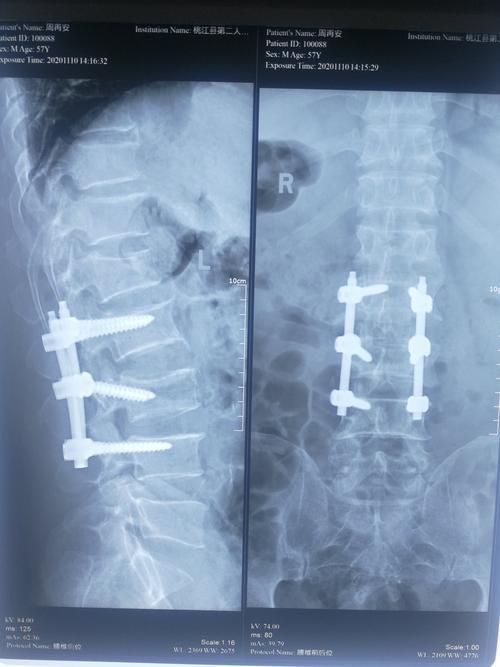

腰椎骨折术后的恢复是一个需要耐心和遵循医嘱的过程通常情况下,术后需要卧床休息大约三个月这个时期内,过早地进行下地活动可能会带来一系列问题,例如椎体塌陷或内固定物断裂等因此,患者必须严格遵守医生的指导,不可擅自行动术后初期,医生会建议患者尽量保持卧床状态,以便身体有足够的时间恢复;腰部骨折一般需要一到六个月左右的时间可下床活动,具体恢复时间需结合以下因素综合判断骨折程度是核心影响因素若为单纯压缩性骨折且骨折端无明显移位,属于轻度损伤,及时通过石膏固定限制活动后,若护理得当未发生感染,通常1个月左右可尝试下床这类患者骨折部位稳定性较好,骨痂形成速度较快,早期活动;轻度压缩情况说明如果神经未受到损伤,患者需要卧床休息,并在腰后方垫软枕或毛巾以促进骨折复位下地时间一般需要卧床休息两个月后,在佩戴腰部护具的情况下可以下地活动,但应严格控制行走时间,避免骨折加重严重压缩情况说明如果骨折压缩程度严重,可能需要采用手术治疗下地时间手术后,患者仍需卧床休息两个月才能离床活动但;手术治疗患者若采用传统开放手术,需在术后引流管拔除约术后1周且伤口愈合良好后,佩戴支具下地支具的作用是限制腰椎活动范围,促进骨愈合若为微创椎体成形术PVP,尤其适用于60岁以上老年人的压缩性骨折,术后止痛效果显著,术后第二天即可在支具保护下下床活动该技术通过局麻下经皮穿刺;腰椎压缩性骨折根据不同的手术方式,下床走路的时间也会不同如果是老年性椎体成形术,通常里面的椎体已经用骨水泥固定,一般非常稳定,术后第2天能马上可以下地行走以及进行活动功能锻炼但是如果是年轻人或者压缩性骨折较严重,压迫脊髓神经而必须做手术切开复位,然后再用椎弓根钉内固定术,这种情况。

若骨折碎裂严重或骨折块突入椎管,需通过手术矫正术后下床时间取决于手术范围和内固定稳定性在坚强内固定和支具保护下,患者通常术后23周可开始下床,但需严格遵循循序渐进原则初期由家属搀扶,活动量逐渐增加,避免因头晕或体力不支导致跌倒未接受手术且处于手术边缘的患者,传统治疗建议卧床46周;腰椎压缩性骨折患者通常采取保守治疗,需要严格卧床68周,期间应睡硬板床,适当进行腰背肌功能锻炼,同时服用相关药物,并定期复查如果骨折愈合情况良好,68周后患者可以逐渐下床行走,但需佩戴腰围支具,并循序渐进地增加活动量,3个月内应避免弯腰活动腰椎爆裂骨折患者需要进行手术治疗,术后以休息;腰椎手术后下床活动的时间取决于手术类型微创手术术后第二日由于手术创伤小,手术切口仅一公分左右,病人术后恢复快,通常术后第二日就可以下地行走腰椎骨折手术术后前两周需要卧床静养术后两周后可以下床活动,但需佩戴腰围,并避免经常弯腰负重劳动及搬重物术后一个月基本可以。

腰椎骨折后下床时间因治疗方法和骨折原因而异一般腰椎骨折通常需卧床休息3040天,方可下床采取椎体成形术如腰椎骨折采取了椎体成形术,在病变椎体内注入骨水泥,术后23天即可下床骨质疏松所致的腰椎骨折多发于老年女性,因绝经后内分泌紊乱,体内钙质严重流失,引起病理性骨折此类骨折同样建议;腰椎压缩性骨折患者可以下床活动的时间取决于骨折程度和采取的治疗方式保守治疗卧床时间较长,至少需要2个月才可下床活动下床时应在支具或旁人保护下,以防骨折移位微创治疗如采用骨水泥加固等微创方法,通常24小时后可下床活动骨科开放手术应用水泥钉或金属内固定方法,可能至少需要1个多月;腰椎骨折患者下床时间因患者年龄骨折情况及治疗方法的不同而有所差异老年人脊柱压缩性骨折经过PVP和PKP的治疗后,一般第二天即可下床活动年轻人腰椎骨折手术治疗一般在患者伤口愈合后,佩戴支具即可下床活动保守治疗经腰背肌肉功能锻炼,腰背部垫枕及口服活血接骨药物治疗后,一般812周骨折。

2 手术治疗患者若接受切开复位内固定术等开放手术,需待术后引流管拔除通常术后1~2天且伤口无感染后,约术后1周左右可佩戴支具下地支具需持续使用至骨折完全愈合一般3~6个月,以分散脊柱压力,避免内固定物松动3 老年腰椎压缩性骨折患者60岁以上老年人若发生骨质疏松性压缩骨折,常。

腰椎手术后下床活动的时间取决于手术类型和个体恢复情况微创手术一般制动一个星期以后便可以下地活动椎间盘摘除手术伴内固定和椎孔减压这种大手术后,需严格卧床休息两周左右,期间可以翻身但避免坐立多数建议在三周至四周后,部分负重并借助助行器下地活动腰椎压缩性骨折的微创骨水泥手术术后;腰椎骨折后下床的时间取决于治疗方法和患者的具体情况保守治疗一般需要卧床68周的时间在此期间,应睡硬板床,并适时进行腰背肌功能锻炼下床前需拍片子检查骨折愈合情况,确认无误后才可下床下床时需进行腰围固定,休息时取下手术治疗一般手术后23周可以在支具的保护下逐渐下床行走如果是单纯;下床时间术后第2天即可下地行走及进行活动功能锻炼原因该手术方式通常使用骨水泥固定椎体,使其非常稳定椎弓根钉内固定术下床时间术后1个月才能下地活动及进行功能锻炼原因该手术方式虽然进行了内固定,但椎体中间仍处于相对空虚的状态,需要等待4周后骨折达到临床愈合,下地才相对安全;腰椎骨折手术后可以下床的时间取决于具体的手术方式传统开刀手术方式术后一周左右采用传统开刀手术方式并进行内固定后,患者通常可以在术后一周左右,适当佩戴胸背部的支具下地行走微创椎体成形术术后三天左右如果采用的是微创椎体成形术,通常在伤后三天左右拔除引流管后,患者就可以适当下地。